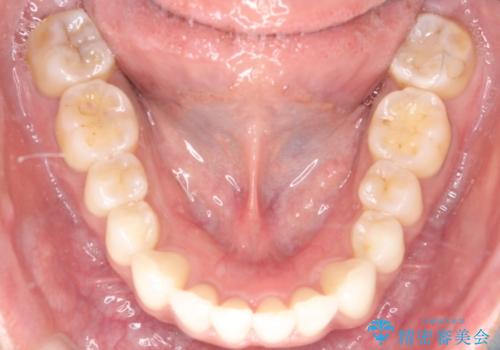

【インビザライン】前歯の凸凹をIPRで改善

- 前歯の凸凹を主訴に来院されました。

前歯を並べるために歯と歯の間にヤスリを入れてわずかに歯を削ることでスペースを確保しています。

歯と歯の間にヤスリを入れてわずかに歯を削ることでスペースを確保する処置をIPRと呼びます。

当院では拡大鏡を用いて丁寧に処置することで歯冠形態を損なわずに行うことができます。